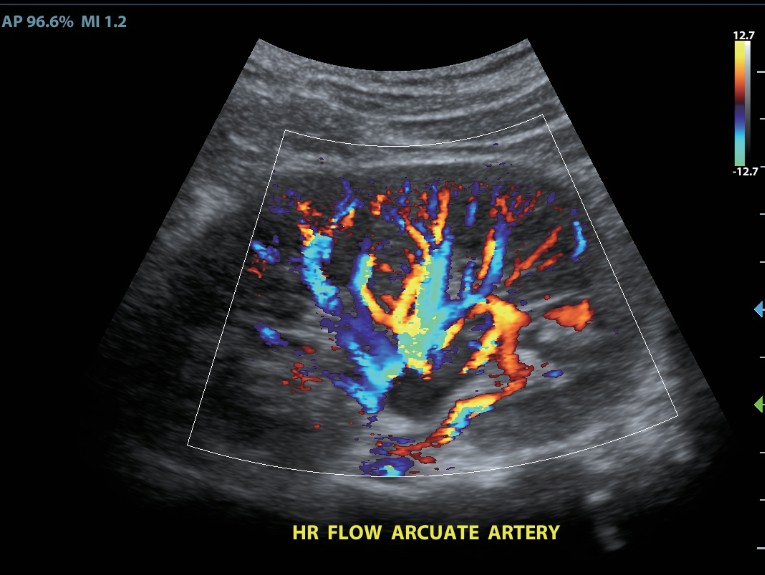

Клинические изображения